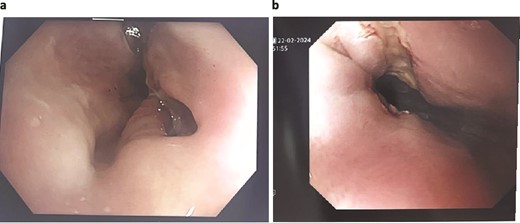

Unfortunately, the patient developed respiratory sepsis and a small bowel obstruction, requiring ICU readmission and intubation. An exploratory laparotomy on postoperative day 5 showed no evidence of ischemia or perforation. A subsequent OGD on postoperative day 8 revealed a 20% staple line defect (Fig. 4a), leading to VACStent and right chest drain insertion.

Patient Four: (a) Before VACStent insertion, showing the oesophageal defect. (b) After VACStent treatment, demonstrating successful defect closure.

Following the removal of the VACStent on postoperative day 13 (Fig. 4b), the patient underwent a prolonged antibiotic course and received dietician support for jejunal feedings. Despite complications, including unsuccessful extubation and bilateral pleural effusions, the patient gradually improved with comprehensive care. A drain was placed on postoperative day 23 to address chest wall collections, and the patient was weaned off the tracheostomy by day 31. The patient continued to recover, managed hypertension, and was discharged home on day 82, with various supports in place and a follow-up scheduled in the clinic.